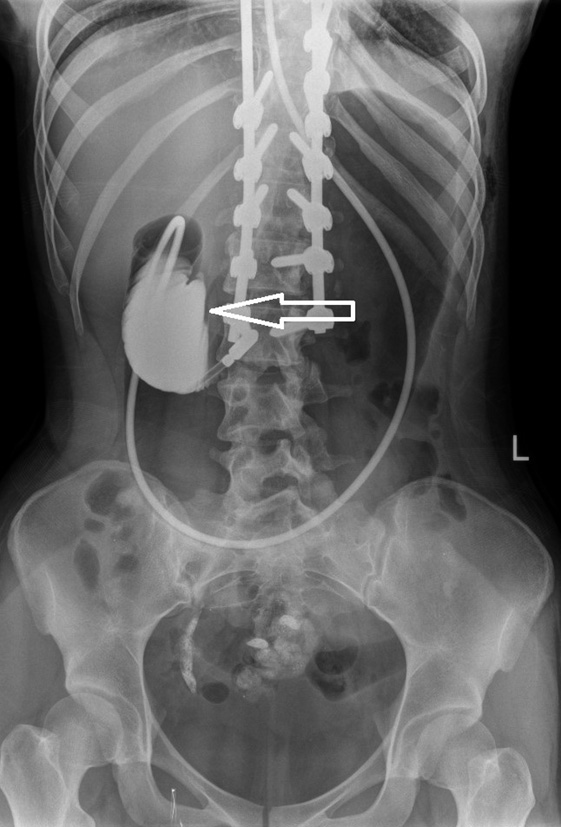

An X-ray examination of the abdominal organs with oral administration of a contrast agent was performed (Fig. 3), which revealed large curvature of the stomach in the upper border of the small pelvis, paresis, and moderate gastric dilatation. No signs of intestinal obstruction were found. An ultrasound examination of the abdominal organs showed no signs of acute surgical pathology.

Fig. 3. Radiograph of abdominal organs with oral administration of a contrast agent

Therapy of paresis and acute gastric dilatation was started, including gastric decompression (nasogastric tube), infusion therapy with electrolyte administration and partial parenteral nutrition, antiemetics (metoclopramide, ondansetron), prokinetics (ipidacrine), prolonged epidural blockade, cleansing enemas, and symptomatic therapy.